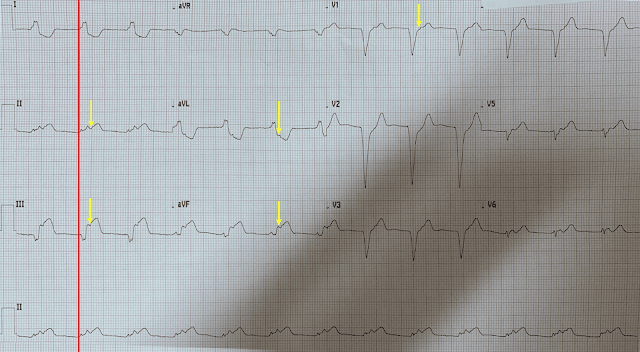

Алкоголик среднего возраста жаловался на слабость и неопределенный дискомфорт в животе. Предыдущая ЭКГ пациента была записана 4 года назад и была полностью нормальной. Вот его текущая ЭКГ:

• Имеется синусовый ритм и блокада правой ножки.

• Имеется высокий зубец R в V2 и V3 и немного избыточная депрессия ST в отведении V2 с двухфазным Т.

Что это такое? Это ишемия? Это задний ИМпST? Что ВЫ думаете? Ответ ниже.

Вот размеченная ЭКГ:

Вершина зубца T видна в V1 (зубец инвертирован). Если вы проведете линию вниз к V2, вы увидите, что низшая точка отрицательной волны совпадает с пиком зубца T в V1. Положительный сегмент зубца Т возникает позже. Итак, эта положительная волна - это зубец U, а не двухфазный зубец T. Стрелка в V5 показывает небольшой горб, который также является зубцом U.

Если бы зубец U действительно был зубцом T, то QT составлял бы 0,44 с, а QTc - 0,568 с, что очень долго. Если интервал QT кажется слишком длинным, подозревайте зубец U.

Ишемии миокарда у пациента не было. Калий оказался на уровне 2,2 ммоль/ л.

Заключение: зубец U вследствие гипокалиемии на фоне блокады правой ножки пучка Гиса.